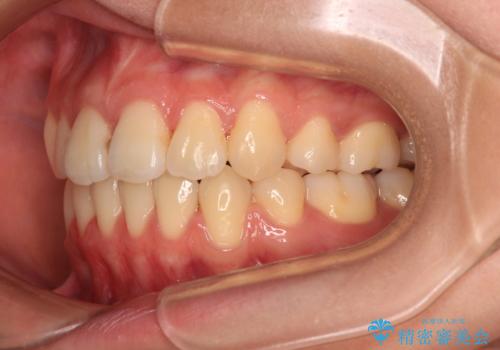

- 抜歯矯正の後戻りを気にして来院された患者様です。

舌の突出癖によるオープンバイトになっていたため、インビザラインによるマウスピース矯正をおすすめしましたが、自己管理の自信がないとのことで、ワイヤー装置による矯正治療を行うこととしました。

舌の突出癖が認められると、上下前歯の隙間を閉じることができません。

舌のトレーニングをしっかりと行っていただくことで、歯列を整えることができます。